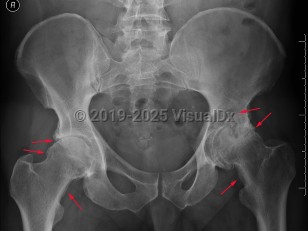

Osteoarthritis is a progressive, degenerative joint disease caused by destruction of joint cartilage and subsequently underlying bone. It is the most common form of arthritis and is thought to be caused by biochemical changes and biomechanical stresses affecting articular cartilage with ongoing use. Common areas of occurrence are the hands, spine, hips, and knees.

Although most patients present with joint pain, stiffness (limited range of motion), tenderness, and lack of flexibility, the age of presentation and temporal progression of disease is variable, driven in part by use / overuse. Joint bones may rub against each other, creating a grating sound, or small bone fragments may form spurs in the joints. Factors affecting deterioration of joint cartilage are older age, obesity, certain occupations, family history, and congenital bone malformations. Associated illnesses are diabetes, gout, and rheumatoid arthritis.